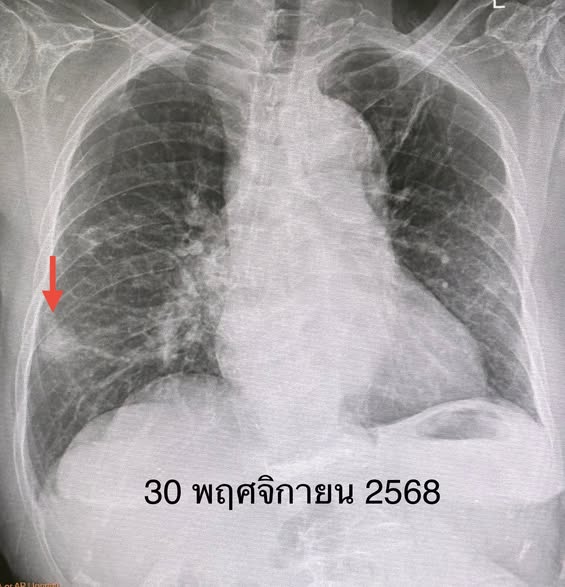

ผู้ป่วยรายนี้เข้ารับการตรวจสุขภาพประจำปี แพทย์ตรวจร่างกายไม่พบไข้ ฟังปอดปกติ แต่การเอกซเรย์ปอดพบเงาผิดปกติบริเวณปอดข้างขวาด้านบน ซึ่งเป็นร่องรอยจากการเคยป่วยวัณโรคในอดีต นอกจากนี้ยังพบก้อนใหม่ขนาด 1.9 x 1.9 เซนติเมตรที่ปอดข้างขวาด้านล่าง ซึ่งไม่เคยพบมาก่อนในปีก่อนหน้า เมื่อทำเอกซเรย์คอมพิวเตอร์ปอด พบว่าก้อนดังกล่าวมีขนาดใหญ่ขึ้นเป็น 3.0 × 2.4 × 2.0 เซนติเมตร